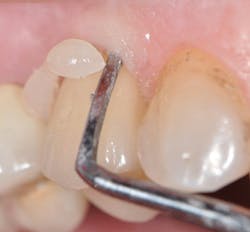

Zirconia can be made a better candidate for bonding when treated with airborne particle abrasion and tribochemical silica coating (Danville's SilJet).6 Lithium disilicate is best pretreated with hydrofluoric acid. Unfortunately, these pretreatment regimens are compromised by saliva after trying them intraorally. Prior to final cementation, I recommend decontaminating the restoration using a product such as Ivoclar's Ivoclean (figure 3). A silanating agent (e.g., Monobond Plus from Ivoclar Vivadent)2 is then placed inside the ceramic restoration (figure 4).

Figure 4: Place silanating agent, allow to react for 60 seconds, and then disperse excess by air drying.